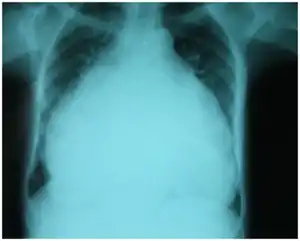

The diagnosis of TR may be suspected if the typical murmur of TR is heard. Severe TR may be suspected if right ventricular enlargement is seen on chest x-ray, and other causes of this enlargement are ruled out.

Chest-Xray: enlarged heart in TR and mitral valve disease

Chest-Xray: enlarged heart in TR and mitral valve disease Transthoracic echo: enlargement of the right atrium in TR and mitral valve disease